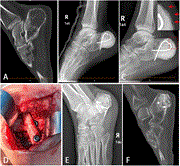

Bone defect reconstruction using Masquelet technique for calcaneal chondroblastoma: a case report

Xianwei Chen and others

Journal of Surgical Case Reports, Volume 2023, Issue 7, July 2023, rjad401, https://doi.org/10.1093/jscr/rjad401